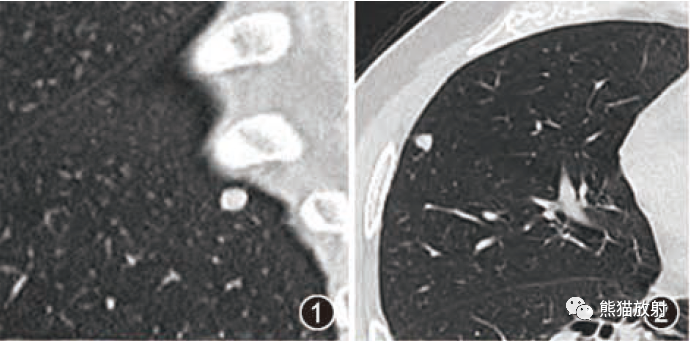

▲病例2:肝母细胞瘤。图1:CT平扫肝左右叶肿块,呈低密度,内部密度不均。图2肝内可见钙化灶。图3增强扫描肝内病灶不均匀明显强化,片状或结节状强化,见假包膜结构,图4可见肝内转移灶。